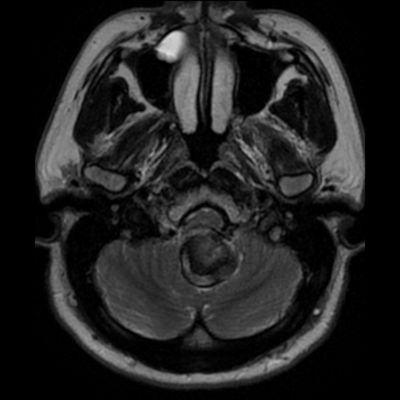

- A. Posterior fossada, T2A, T1A görüntü ve SWAN sekanslarda, 3.5 cm boyutta, düzgün sınırlı, T1A hiperintens, T2A hipointens heterojen iç yapıda kitlesel lezyon izleniyor (çember). Lezyonun serebellum ve kraniyoservikal bileşkeye bası etkisi mevcuttur (ok). Lezyon periferinde T1A, T2A ve SWAN görüntülerde hiperintens tubuler yapı bulunmaktadır (ok). Bu yapı intralezyonel “yılanvari eksantrik vasküler’’ yapıdır.

- Kısmen tromboze olmuş dev serebral anevrizma, kan ürünlerinin değişken yaşına bağlı olarak MRG’de heterojen bir sinyale sahiptir.

- T2 kısmen tromboze anevrizmada genellikle hipointens odaklarla heterojen, serpantin anevrizma içi damar kanalında akım boşlukları, bitişik parankimde vazojenik ödem görülebilir.